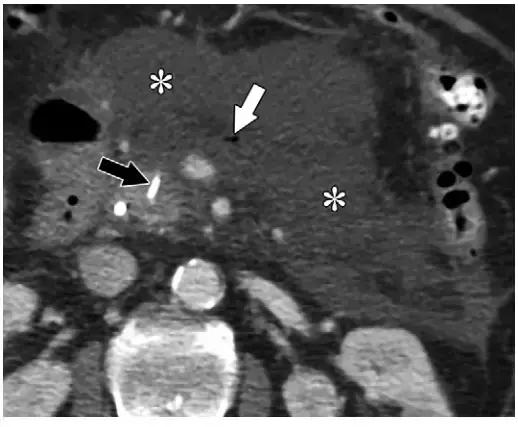

如果坏死物侵袭肠管,致使出现胰肠管瘘,感染的内容物里的气体也可来自肠道,多见于结肠和十二指肠(图 13)。

急性胰腺炎入院的患者中约 4% 会出现胰肠管瘘。胰管内气体多见于内镜胰管照影或胰管支架术后(图 14)。

图 13 74 岁女性坏死性胰腺炎患者。发病 5 周增强轴位 CT 可见多发气体影(*)。可见横结肠远端与病变形成瘘管,含有气体和液体(箭头),可以解释 WON 含有气体的原因

图 14 59 岁男性坏死性胰腺炎患者,发病 3 周增强 CT 轴位图像可见胰颈、胰体、胰尾(*)和胰周坏死。近期导管内支架植入术(黑箭头)引起胰管内少量气体影(白箭头),这并不代表 ANC 感染